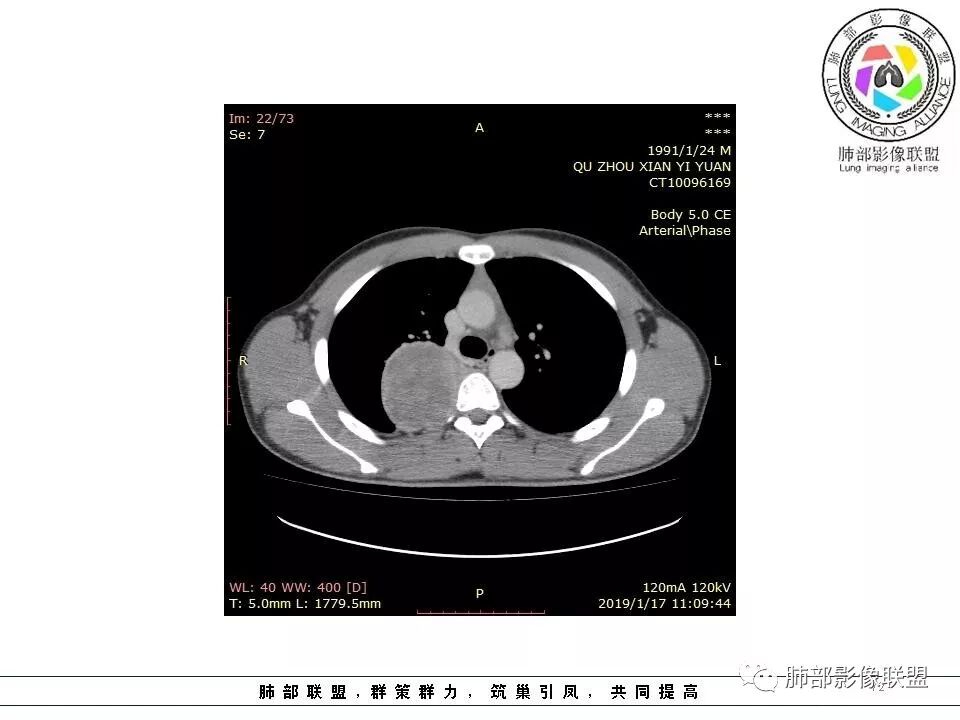

1.右上胸内脊柱旁类圆形肿块,质地似乎比较坚实,密度稍显不均,但未显示明确的坏死。

如此密度形态的病灶位于肺边缘首先应当想到孤立性纤维瘤,可相邻胸膜未见明显的异常强化和胸膜方向延伸。

注意所谓“胸膜尾征”的概念及形成机制与“脑膜尾征”是大不相同的。

2.肋间动脉病供血也提示肿块来自后纵隔?

3.相邻椎间孔未见扩大,也未见块影延入椎管,易起自于神经根的鞘瘤似乎找不到支持点。

可惜未提供矢状位骨窗图像,如在肋骨内下缘观察到压迹有助于肋间神经的鞘瘤的判断,这是因为二者之间密切的毗邻关系。

4.静脉期轻度不均匀强化,注意不是环形强化,亦未见明确的“AB区”,这点也不支持神经鞘瘤。临床及病灶轻度强化都不支持副节瘤。

尽管神经纤维瘤的诊断确实有些出乎意外,但病例开阔了我们的视野。